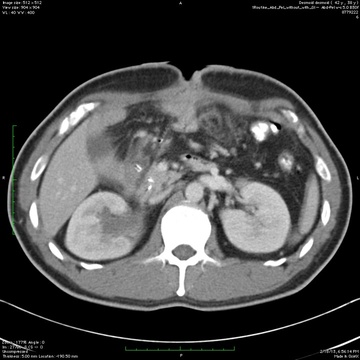

КТ брюшной полости с контрастом

КТ брюшной полости (Полное название мультиспиральная компьютерная томография брюшной полости) с контрастом применяют для обследования состояния органов, тканей и лимфатических узлов при подозрении на опухолевые или воспалительные заболевания...